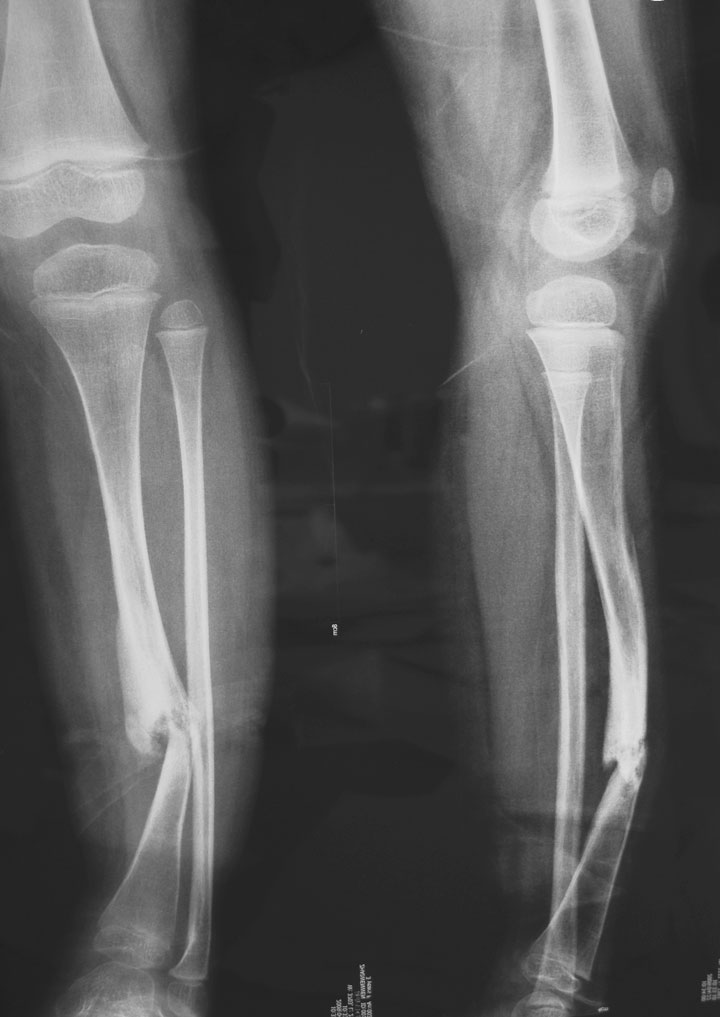

以下是引用拾荒者在2009-4-26 22:21:00的发言:[br]胫骨前弓状变形,中下1/3处骨质不连续,远端骨吸收呈笔尖样改变,局部骨皮质增厚,结合病史支持先天性胫骨假关节。谢谢11楼的精彩点评!

以下是引用jfl19591015在2009-4-25 14:18:00的发言:[br]像陈旧性骨折畸形愈合,形成假关节.但也不除外先天性胫骨假关节可能.